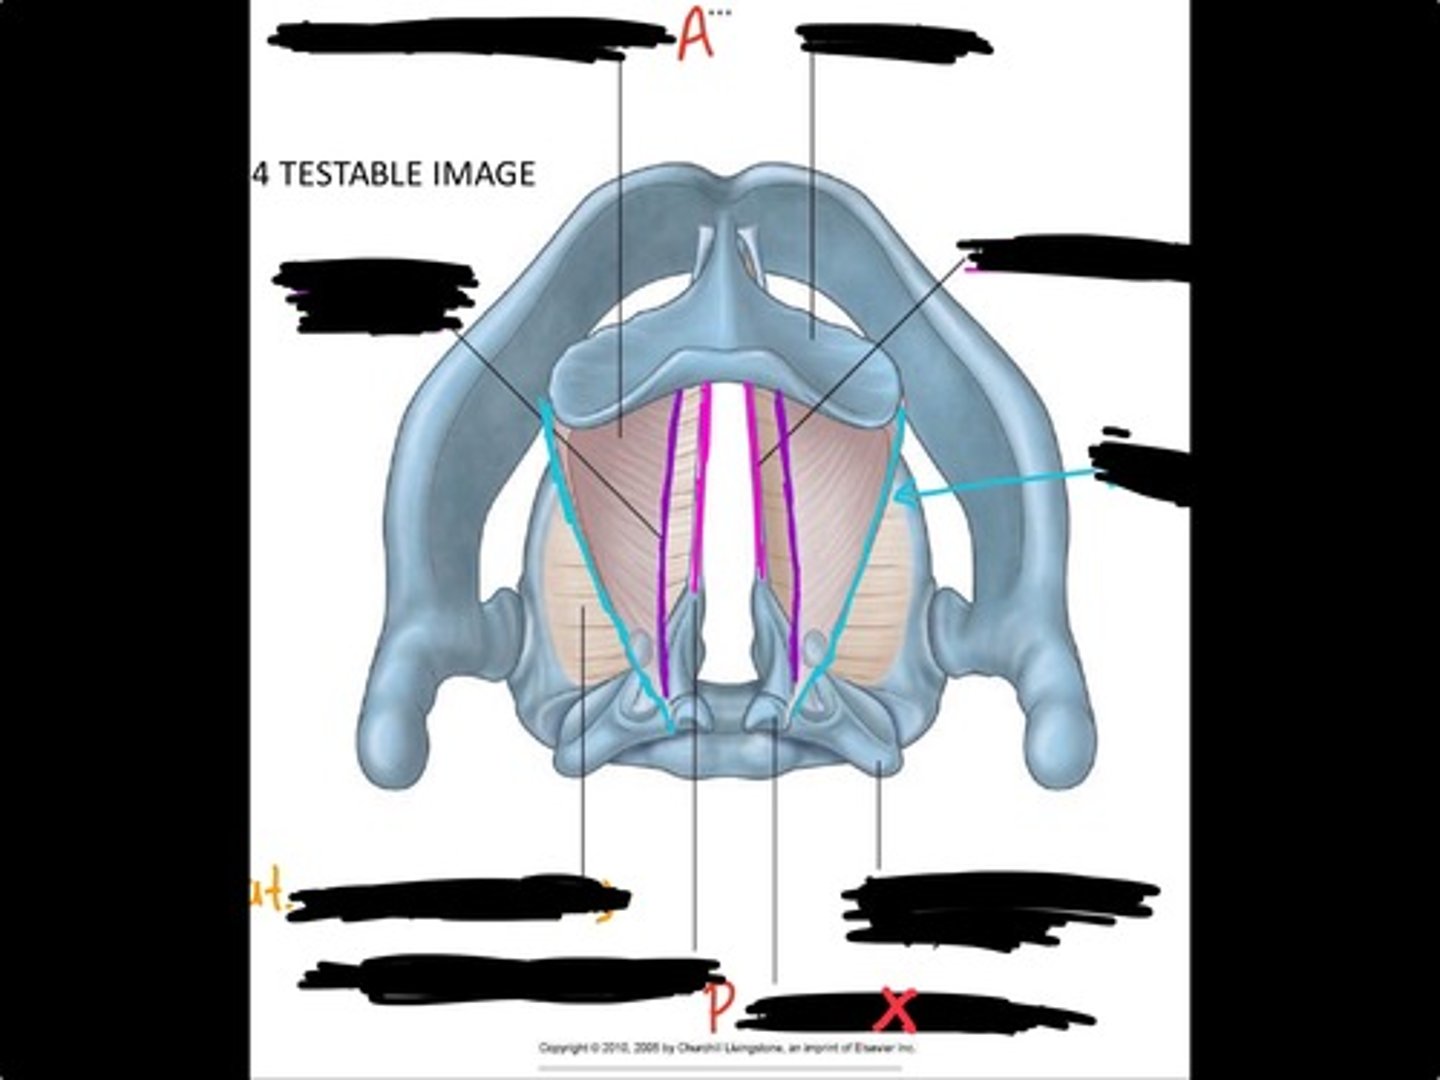

Vocal process of arytenoid

Conus elasticus

Vestibular ligament

Quadrangular membrane

Epiglottis

vocal ligament

Aryepiglottic ligament

Muscular process of arytenoid

Corniculate cartilage

Posterior crico arytenoid

oblique arytenoid

transverse artyenoid

Rima glottidis

Vocal ligament

Vocalis muscle

Lateral cricothyroid ligament

Lateral cricoartenoid